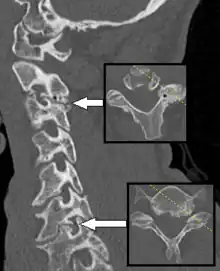

Axial skeleton and extremities

For the axial skeleton and extremities, CT is often used to image complex fractures, especially ones around joints, because of its ability to reconstruct the area of interest in multiple planes. Fractures, ligamentous injuries, and dislocations can easily be recognized with a 0.2 mm resolution.[69][70] With modern dual-energy CT scanners, new areas of use have been established, such as aiding in the diagnosis of gout.[71]

Multiplanar reconstruction and projections

Multiplanar reconstruction (MPR) is the process of converting data from one anatomical plane (usually transverse) to other planes. It can be used for thin slices as well as projections. Multiplanar reconstruction is possible as present CT scanners provide almost isotropic resolution.[105]

MPR is used almost in every scan. The spine is frequently examined with it.[106] An image of the spine in axial plane can only show one vertebral bone at a time and cannot show its relation with other vertebral bones. By reformatting the data in other planes, visualization of the relative position can be achieved in sagittal and coronal plane.[107]

New software allows the reconstruction of data in non-orthogonal (oblique) planes, which help in the visualization of organs which are not in orthogonal planes.[108][109] It is better suited for visualization of the anatomical structure of the bronchi as they do not lie orthogonal to the direction of the scan.[110]